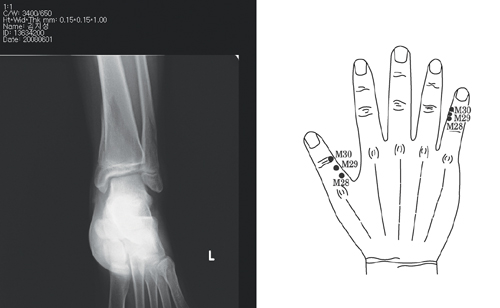

사고 당시 손상된 성장판 사진

▲ 사고 당시 손상된 성장판 사진

2008년 6월 1일 당시 중학교 3학년이던 아들이 불의의 사고로 다리를 다쳐 병원에서 여러 가지 검사와 더불어 MRI 사진도 찍었는데, 성장판이 많이 열려있는 상태에서 경골과 비골이 골절되고 성장판까지 손상돼 수술이 불가피하다는 것이었다.

또 M28ㆍ29ㆍ30인 수지 상응점에 -도자로 20분정도 더 조사한 후 PEM으로 상응부위에 계속 자극을 준 후, 기마크봉 은색을 부착하고 경과를 지켜보았다. 서금요법으로 좋은 효과가 꼭 나올 것이라고 마음속으로 기도하면서 자극을 했다.